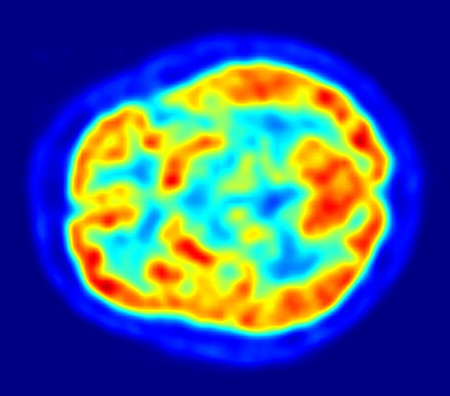

健康脑部的氟代脱氧葡萄糖正子断层扫描。热区表示葡萄糖摄取量较高,基底核的状况能帮助诊断帕金森病。